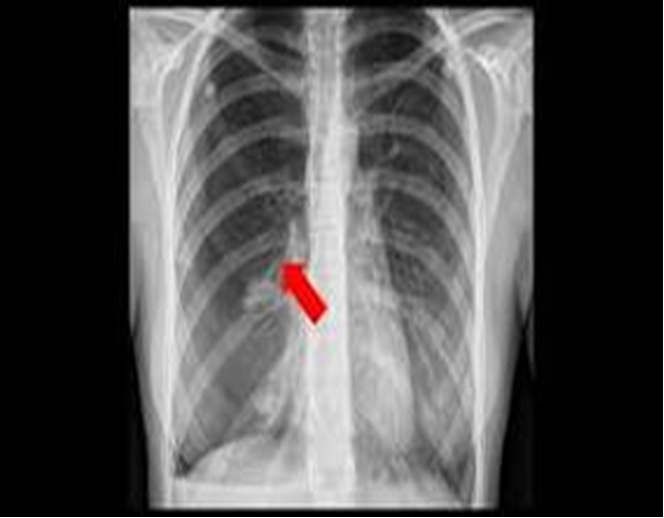

Chest US or CXR, possible CT

Diagnostic Studies of Pleural Effusions